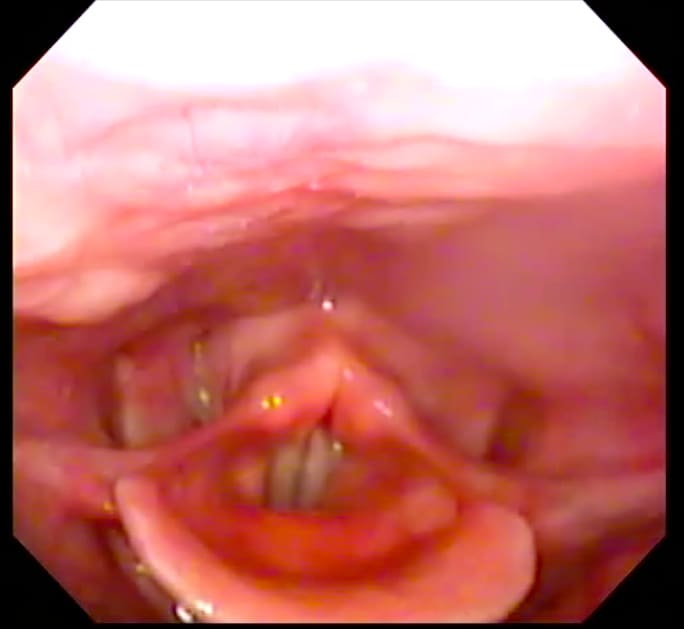

Effortful Larynx